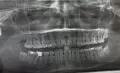

Добрый день! У меня был глубокий кариес в верхней правой семерке. Врач вылечила, поставила пломбу, но боль осталась все равно. Я приехала к ней, после чего она сказала, что это пульпит и удалила нервы. Но боль сохраняется уже 2 недели! Иногда ноет днем, а на ночь, когда ложусь спать, именно в лежачем положении, усиливается. Обезболивающие не помогают. Нет отека, температуры, просто болит зуб. Рентген делала, ходила даже к другому врачу на полный рентген. Говорят, что все в норме. Пожалуйста, подскажите, с чем это может быть связано?